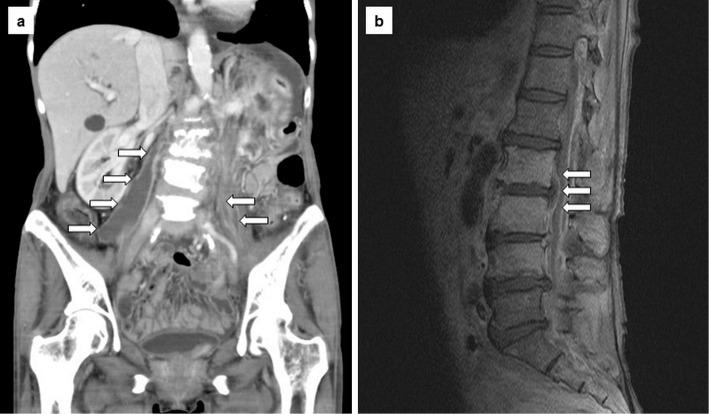

Edwardsiella tarda is commonly isolated from aquatic environments and a variety of animals. We present the first case of E. tarda bacteremia with psoas and epidural abscess. The patient was a 65-year-old woman with recurrent gastric cancer who had frequently consumed raw fish and grilled eel. She was successfully treated with antimicrobials and surgery. We also review reports published in English regarding E. tarda bacteremia in Japan and the experience at our hospital. On the basis of this review, we conclude that the major underlying disease leading to E. tarda bacteremia is malignancy and that the gastrointestinal tract is the most commonly affected organ. The overall mortality rate due to E. tarda bacteremia in our review was 38.1% (8/21). Although E. tarda bacteremia is rare, clinicians should be aware of this fatal food-borne infection.

摘要

迟缓爱德华氏菌通常从水生环境和各种动物中分离得到。我们报告了首例伴有腰大肌和硬膜外脓肿的迟缓爱德华氏菌败血症病例。患者为一名65岁的复发性胃癌女性,经常食用生鱼和烤鳗鱼。她通过抗菌药物治疗和手术成功治愈。我们还回顾了日本关于迟缓爱德华氏菌败血症的英文报道以及我院的经验。基于此回顾,我们得出结论,导致迟缓爱德华氏菌败血症的主要基础疾病是恶性肿瘤,且胃肠道是最常受累的器官。在我们的回顾中,迟缓爱德华氏菌败血症的总体死亡率为38.1%(8/21)。尽管迟缓爱德华氏菌败血症罕见,但临床医生应意识到这种致命的食源性感染。